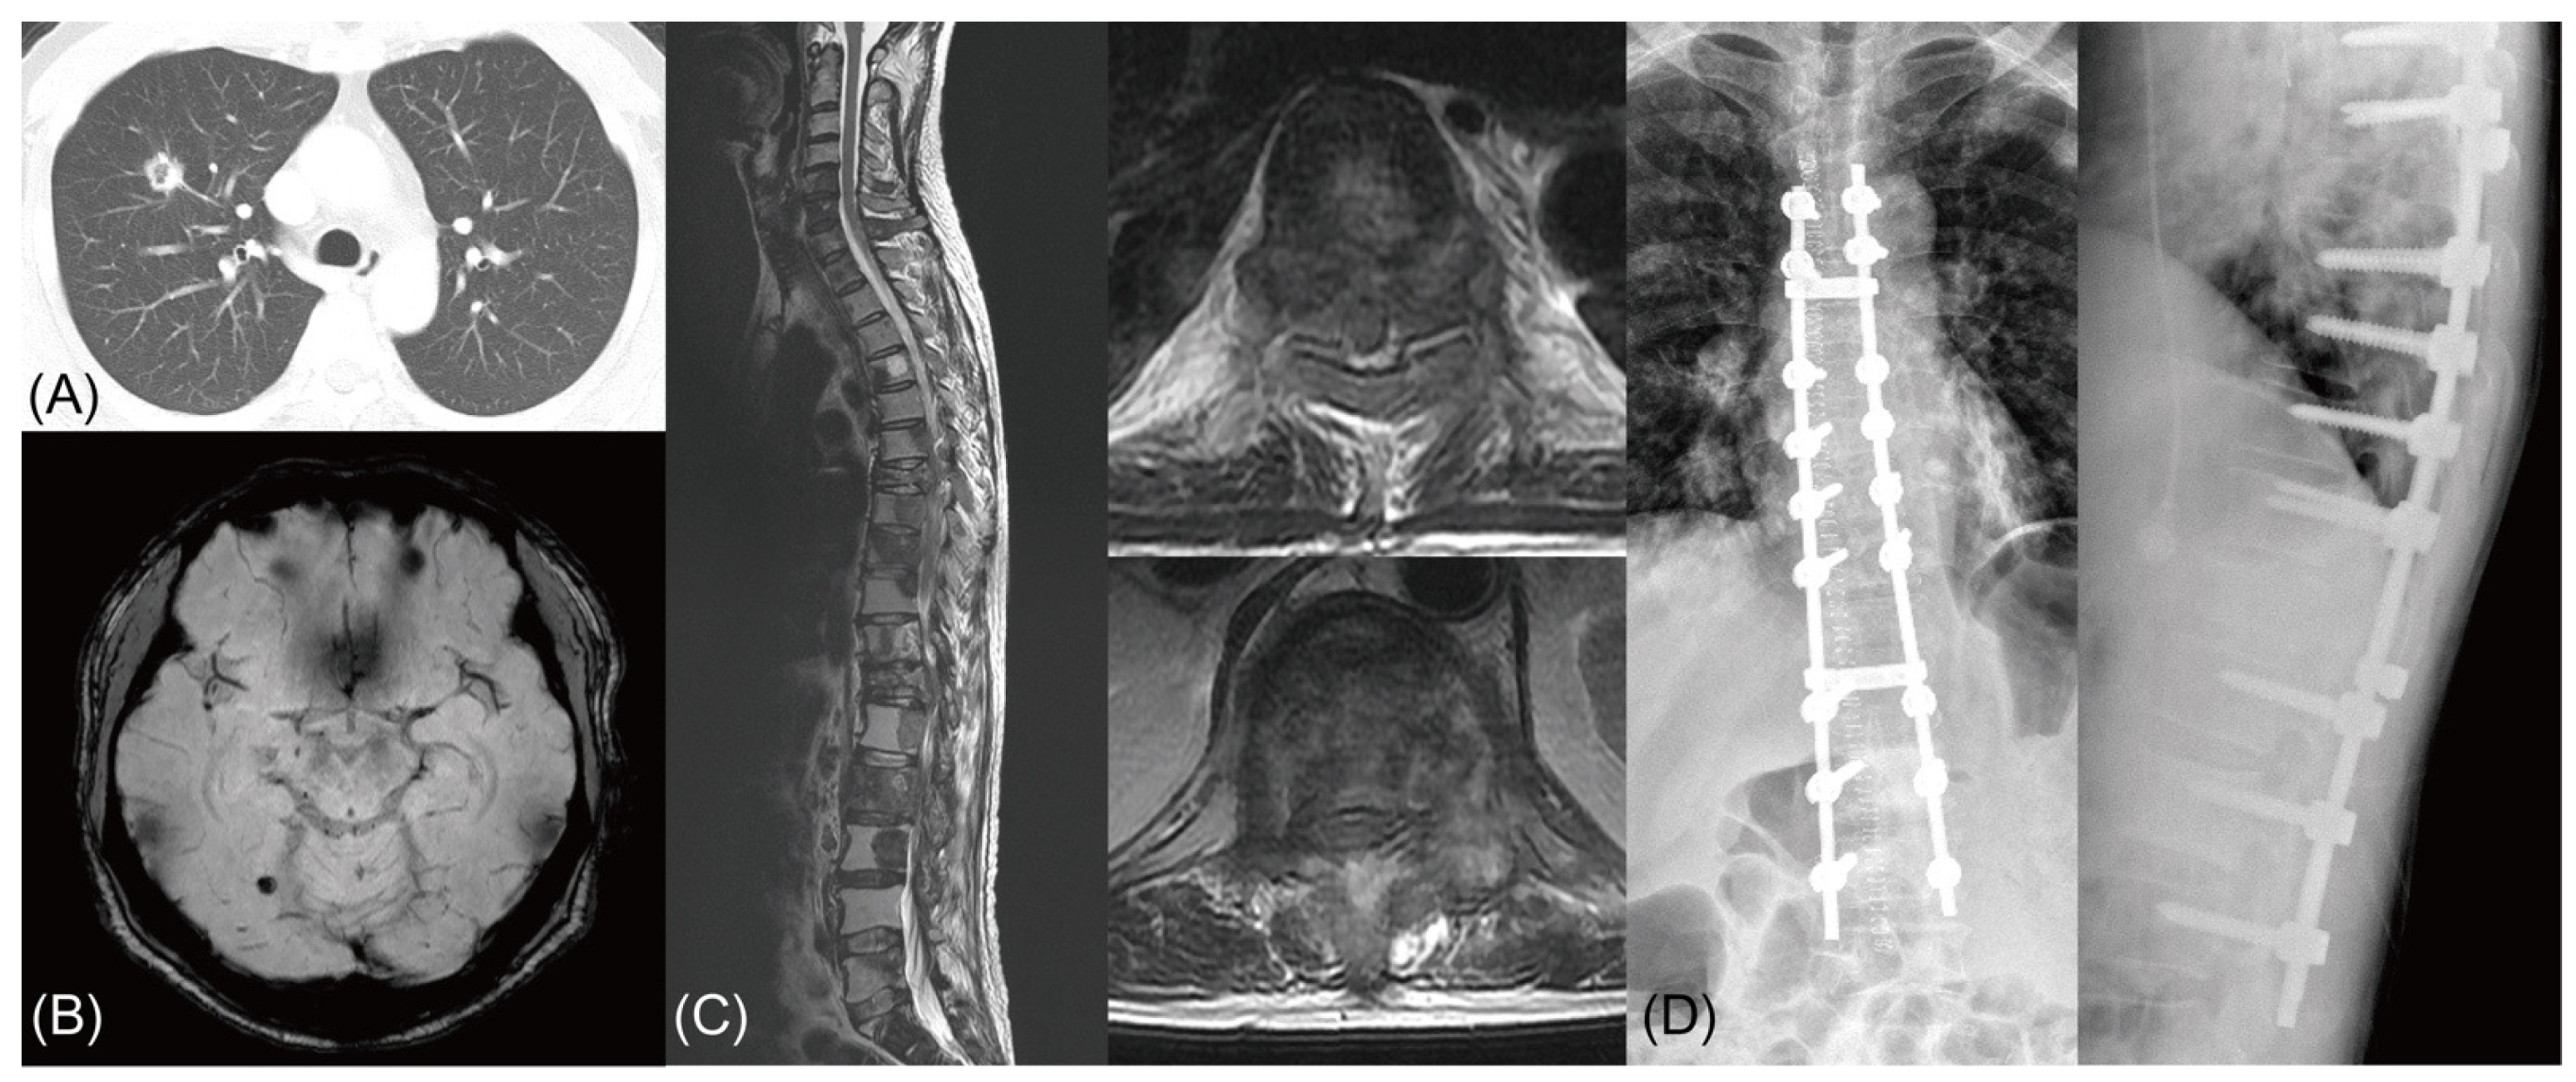

Figure 4. Comparison of Kaplan–Meier curve stratified by the biological factors. An illustrative case of acquired resistance to tyrosine kinase inhibitor (TKI) in an epidermal growth factor receptor (EGFR) mutation-positive non-small cell lung cancer (NSCLC) patient. (A,B) A 53 years-old male with lung adenocarcinoma in right upper lobe. EGFR mutation analysis from the lung specimen showed a microdeletion mutation in exon 19. (C) After 2 years of systemic treatment with multiple regimens including TKI (gefitinib), the patient was diagnosed with multiple spinal metastasis with spinal cord compression at T7 and T12. (D) The patient underwent a palliative decompression and stabilization, and EGFR mutation analysis from a spine specimen revealed a missense mutation of EGFR gene exon 20 (T790M). The patient expired 4 months postoperatively due to disease progression.